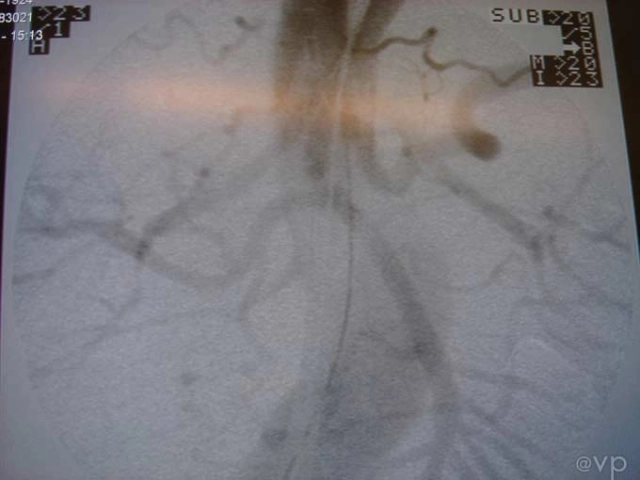

Intestinal